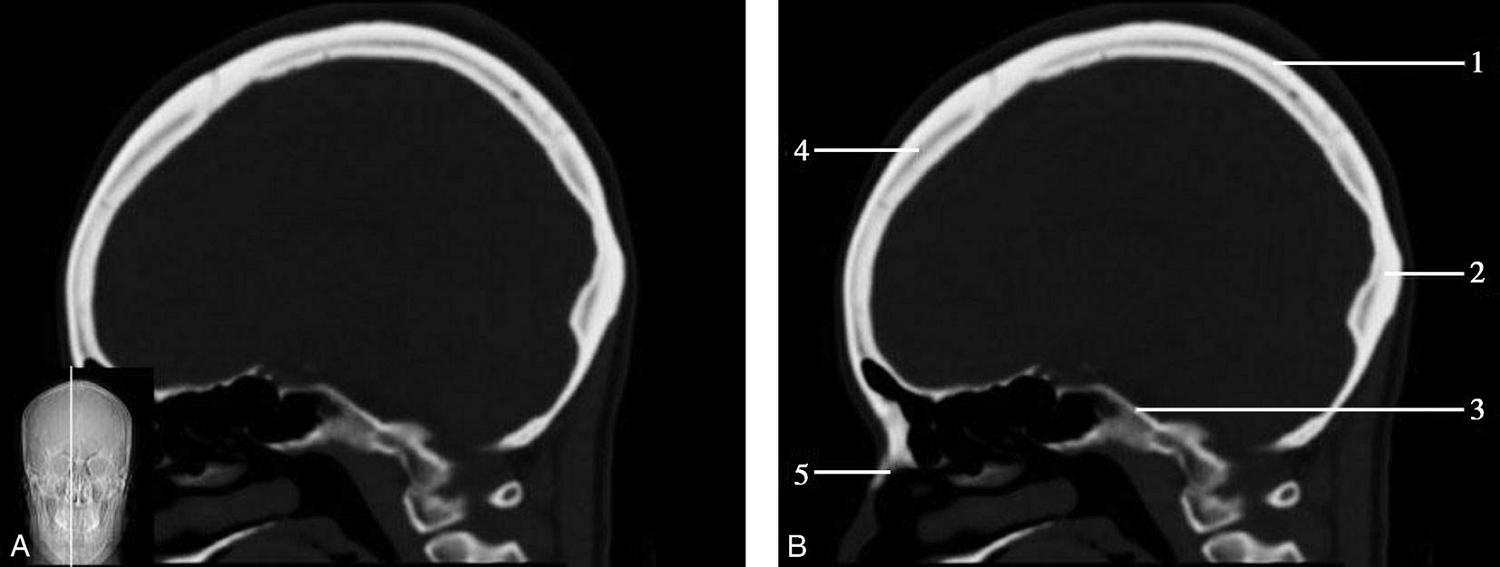

重要结构:胼胝体、垂体、中脑导水管、扣带回、中央沟、第三脑室、斜坡(图1-2-59、图1-2-60)。

图1-2-59 正中矢状面CT

A.矢状面;B.矢状面标注

1.中央沟;2.扣带回;3.胼胝体体部;4.侧脑室;5.中脑;6.胼胝体膝部;7.穹隆;8.第三脑室;9.胼胝体压部;10.垂体;11.中脑导水管;12.第四脑室;13.脑桥;14.蝶窦;15.斜坡;16.小脑扁桃体;17.延髓

图1-2-60 正中矢状面骨窗CT

1.顶骨;2.枕骨;3.斜坡;4.额骨;5.蝶鞍

此层面可显示胼胝体全貌,它位于层面中央区域,是呈上凸下凹的弧形结构,由前向后分为嘴、膝、体和压四部分。扣带回环绕胼胝体上方,扣带沟位于扣带回的上方。大脑半球中部和后部分别可见较深且恒定的中央沟和顶枕沟。中央沟为是额叶顶叶分界标志。

胼胝体下方为侧脑室及穹窿,第三脑室借穹窿与前上方的侧脑室体部分开,背侧丘脑的内侧面以及中脑顶盖分别为第三脑室的外侧壁和底。第三脑室向前籍室间孔与侧脑室相通,向下经中脑导水管通第四脑室。中脑腔狭窄呈管状,即称为中脑导水管,中脑导水管畸形,常见者为导水管的分叉畸形和狭窄,其次可见中脑导水管膈膜,造成先天性脑积水。

脑干由中脑、脑桥和延髓组成,自第三脑室底向下后稍斜行,移行于颈髓。由上至下,脑干腹侧可见脚间池、桥前池和延髓池,脑干背侧可见大脑大静脉池、四叠体池和小脑延髓池。

垂体位于蝶鞍内,其前部为腺垂体,后上部分为神经垂体。垂体下方为鞍底及蝶窦,上缘因鞍膈存在而平直,垂体借垂体柄向上连于丘脑下部。垂体的前上方见视交叉和视束。斜坡作为前颅窝底的重要组成部分与多个重要结构相比邻,矢状位呈三角形,颅内肿瘤或颅外鼻咽部恶性肿瘤均可侵犯至此,原发肿瘤常见为脊索瘤。小脑幕居枕叶和小脑之间,向后下连接窦汇,向前至中脑后方游离,称小脑幕切迹。小脑幕下方为小脑扁桃体。成年人小脑扁桃体下缘由枕骨大孔向下疝入椎管超过5mm称为Chiari畸形,以矢状位显示最佳。